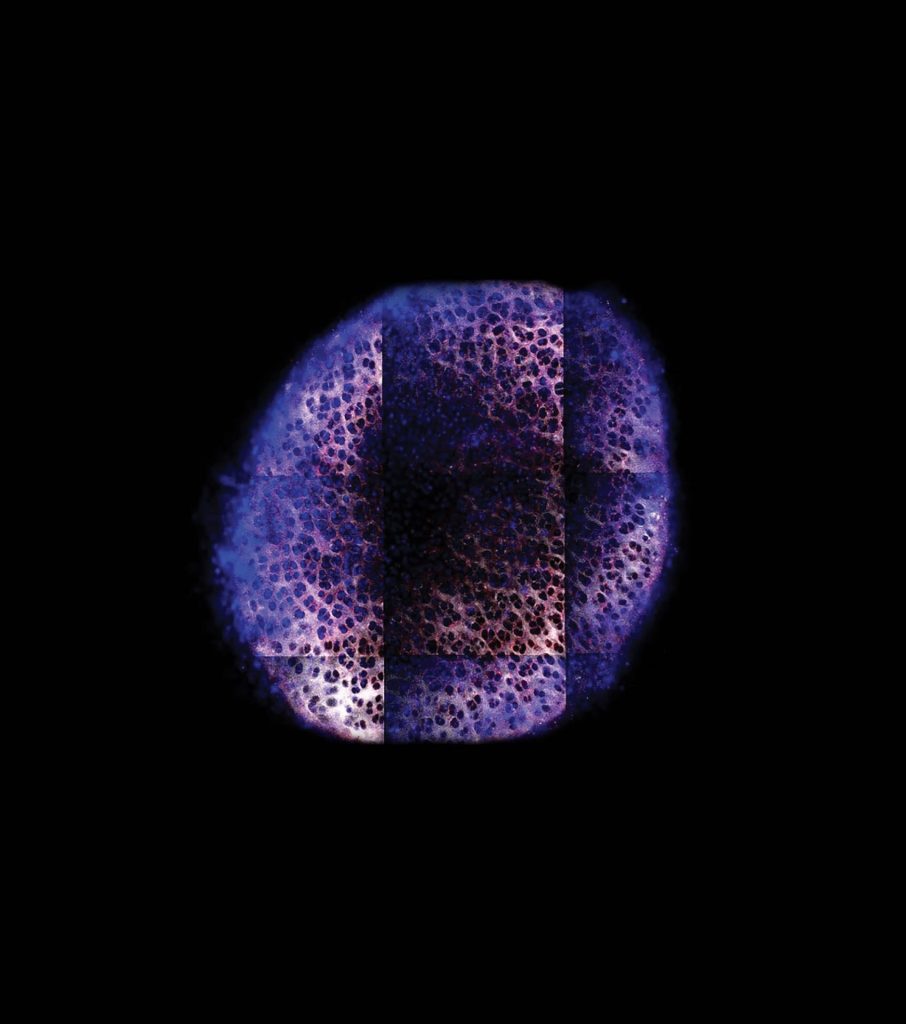

A partire da quell’anno sabbatico più di quattro decenni fa, Grodzinsky apprese un fatto fondamentale sulla cartilagine. Mentre le stesse fibre tissutali forniscono parte del supporto per le nostre articolazioni, gran parte della sua forza deriva dalle sue proprietà elettrostatiche. “Circa la metà della rigidità meccanica alla compressione della nostra cartilagine è dovuta alle interazioni repulsive elettrostatiche tra le catene di zucchero caricate negativamente”, spiega.

Questa matrice tissutale caricata negativamente offre anche un modo per somministrare farmaci direttamente nel tessuto, inserendoli in nanoparticelle caricate positivamente. Il team di Grodzinsky è stato in grado di dimostrare nella cartilagine del ginocchio di cadavere umano che tali particelle possono contrastare l’infiammazione precoce e i danni causati dalle lesioni.

Finora, il laboratorio è stato in grado di ottenere parti ossee di ginocchio, cartilagine e capsula dell’articolazione sinoviale da 45 donatori, afferma la ricercatrice Garima Dwivedi. Nel laboratorio i campioni vengono messi in pozzetti ricavati in piastre di plastica e mantenuti metabolicamente attivi. Quindi si applica un impatto meccanico che imita ciò che accade in un infortunio al ginocchio. In questo modo vengono rilasciate molecole infiammatorie note come citochine e si avvia un processo simile a quello che accade nell’osteoartrite.